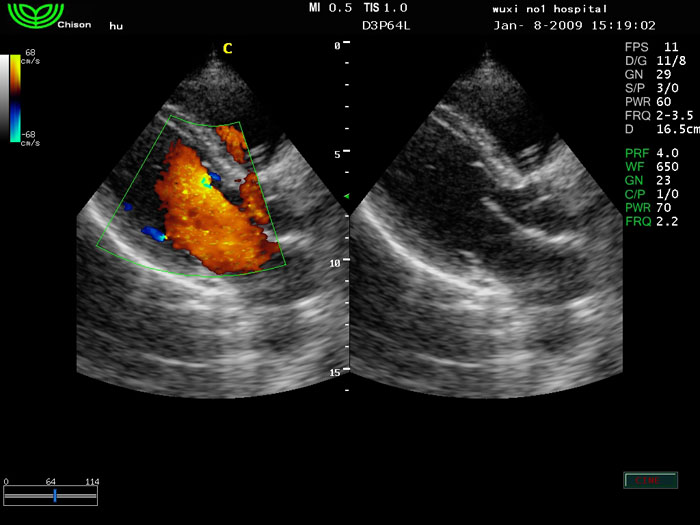

D3P64L 3.0МГц, фазированная решетка.

2.0МГц – 4.4МГц. Применения: кардиология, брюшная полость, акушерство. |